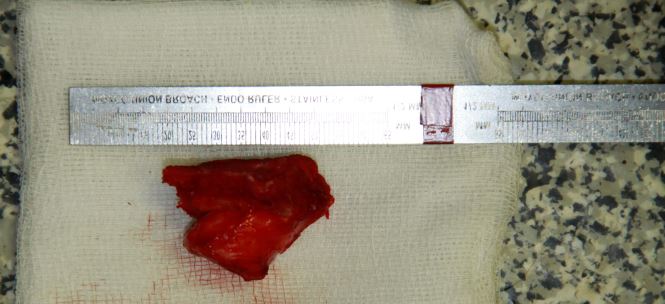

Fig 4 Photograph showing the excised portion of the right zygomatic arch including the abnormal proliferative bone